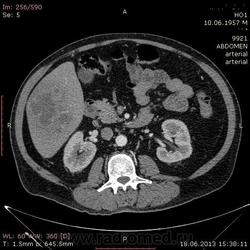

- https://radiomed.ru/sites/default/files/styles/case_slider_image/public/user/17529/img-0007-00001_3.jpg?itok=TEBWqlDr

На абсцесс похоже

На мой взгляд, абсцесс.

Тоже за абсцесс.

Cпасибо , коллеги.Сегодня больного прооперировали диагноз абсцесс правой доли печени.Оказывается больной когда - то получил тупую травму живота, об этом нам не говорил.....